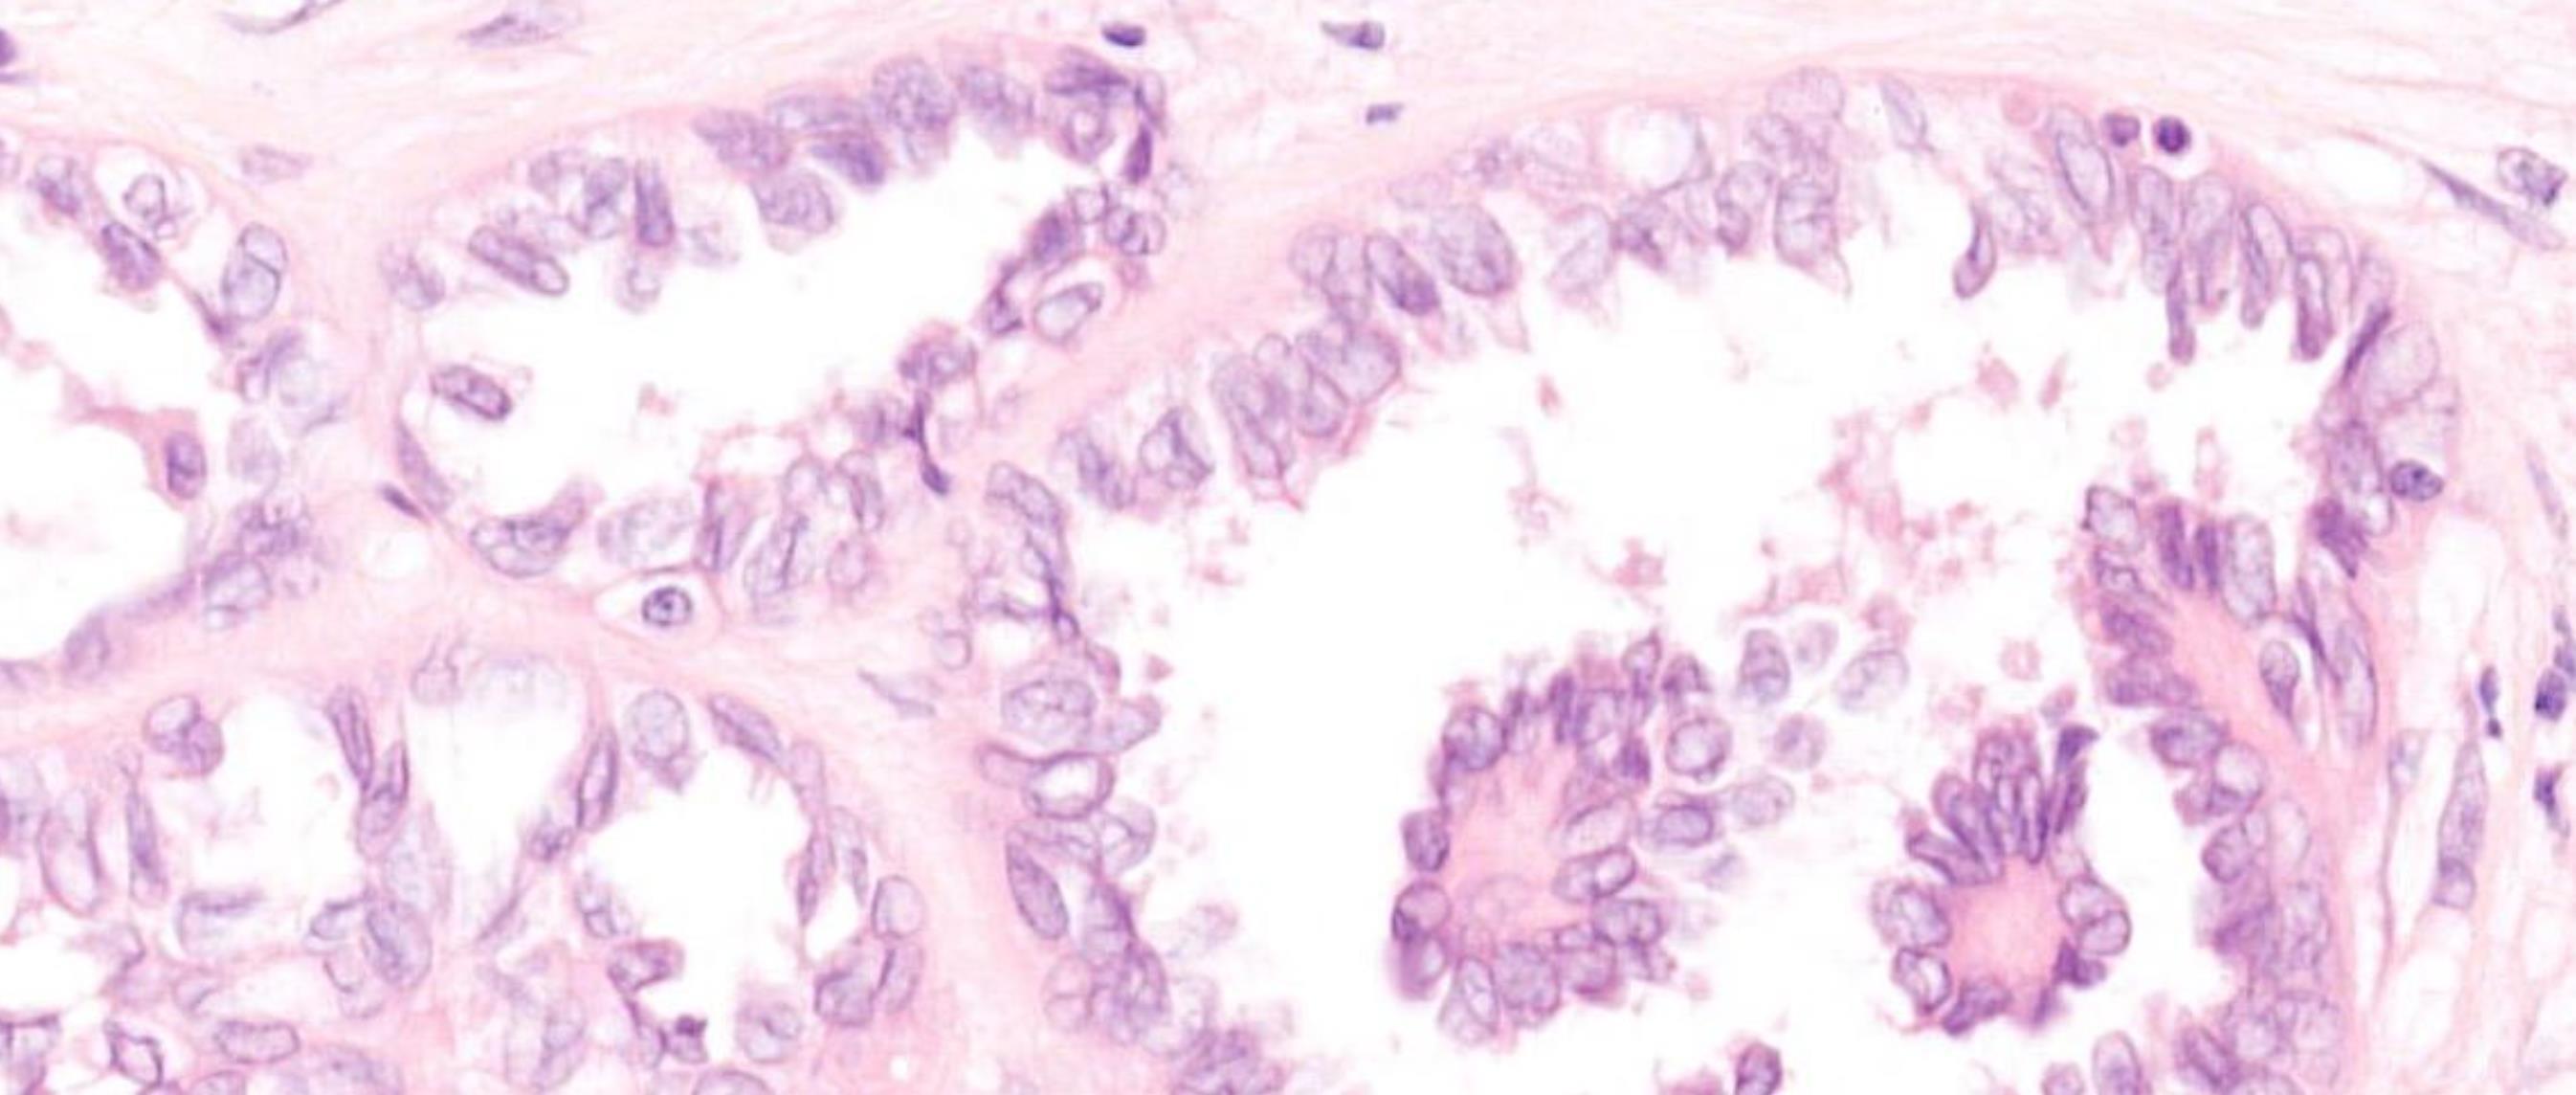

NIFTP

NIFTP is in essence a follicular adenoma with PTC nuclear features

Hyalinizing trabecular tumour (HTT) • Rare benign follicular neoplasm characterized by thick trabeculae and cells with nuclear elements shared with PTC • Interlobular DPAS positive hyaline material • TTF1+,TTG+, calcitonin neg, • Mib1 monoclonal antibody against Ki67membranous stain+

• No BRAF mutations or

were identified in HTT. 2019- GLIS fusions found in 100% of HTT especially PAX8-GLIS3 No BRAF, RAS, RET/PTC found in HTT GLIS3 not found in over 100 papillary carcinomas used in this study

Is HTT a type of PTC?

RAS mutations